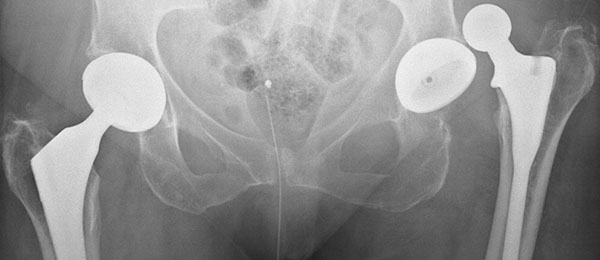

Чаще всего для диагностики используется рентгенография тазобедренного сустава с выполнением в нескольких проекциях. Этот метод позволяет определить положение головки эндопротеза относительно чашки. На рентгеновском снимке видна целостность компонентов и наличие или отсутствие переломов.

При необходимости используют компьютерную томографию. С ее помощью можно более подробно оценить положение имплантата и определить причину вывиха.